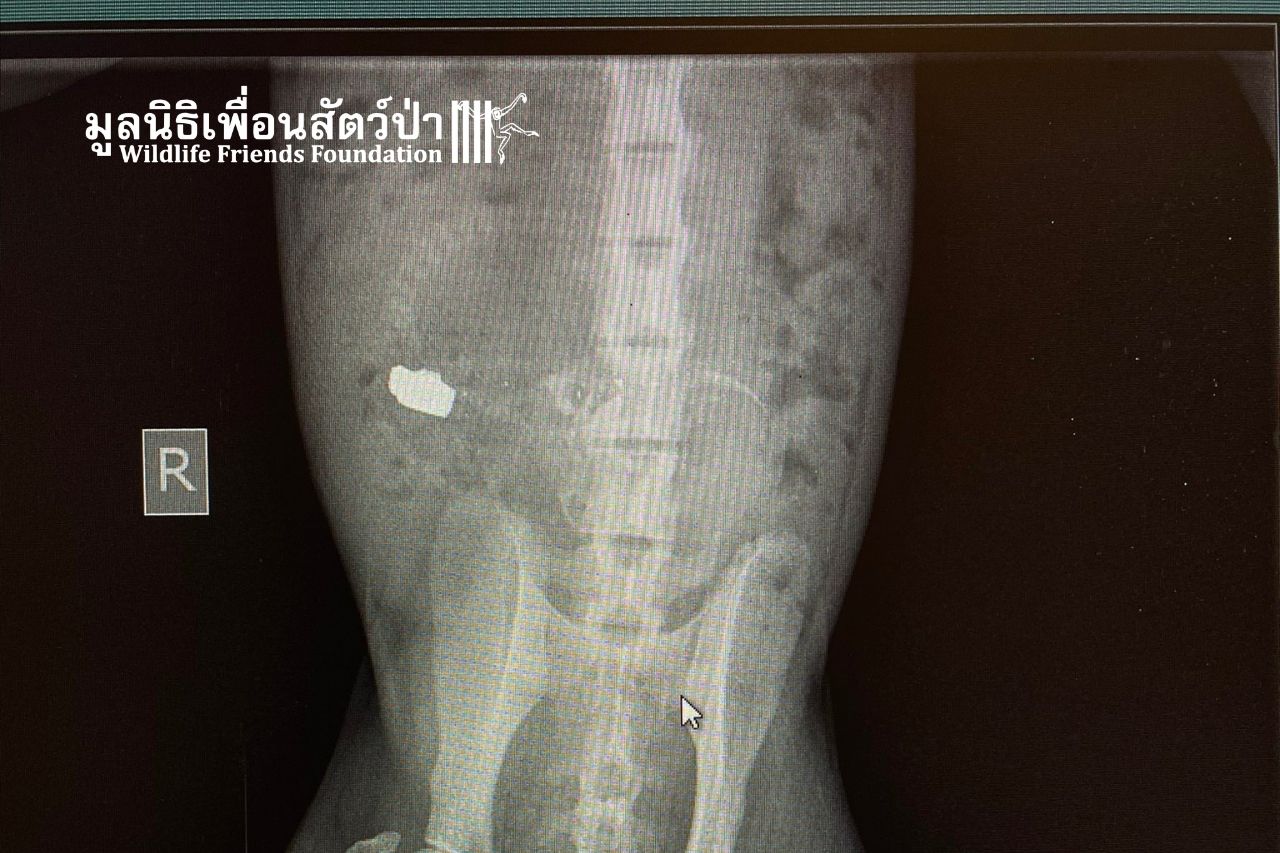

A pregnant female macaque recently arrived at WFFT with a bullet in her spine. Our veterinary team has removed the bullet, but as she is in the late stages of pregnancy, we must monitor her very closely to see if she can deliver on her own, given that we don’t know if she will recover from the damage caused by the bullet.